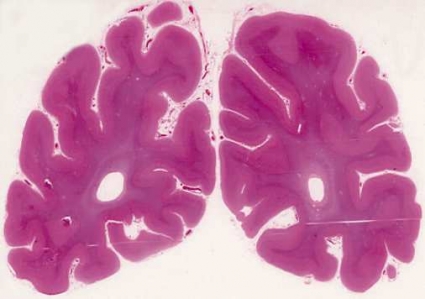

Vid FTD har hjärnan i många fall normal storlek och form trots en uttalad klinisk demensbild. I andra fall syns vidgade fåror mellan avsmalnade vindlingar frontalt, ibland även temporalt (Figur 1). Vaskulära skador är sällsynta.

Mikroskopiska fynd. Patologin vid FTD har paradoxalt nog som »karaktäristiskt« drag att vara relativt lindrig och ospecifik, vilket speglas i en diskret nervcellsuttunning i hjärnbarkens yttre tre lager (Figur 2). I vissa fall begränsas degenerationen till frontala områden (lateralt eller på undersidan, frontoorbitalt), i andra fall är den lindriga kortikala skadan utbredd inom stora delar av temporalloberna och når även parietallobernas främre delar. Framträdande är en degeneration inom det limbiska komplexet, speciellt främre cingulum [2, 32].